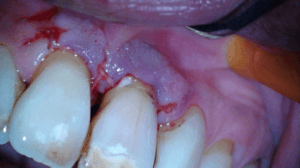

Na het wegfrezen van het losse stukje vulden we het defect op met composiet. We werken de composiet af met fijne diamantjes en handscalers. Een superscherp geslepen handinstrument kan uitstekend worden gebruikt bij het afwerken van composietvullingen. Wel alleen vlak na het polymeriseren, dan is composiet nog te scalen.

Na polijsten hechtten we de flap en maakten we een afspraak voor een week later.